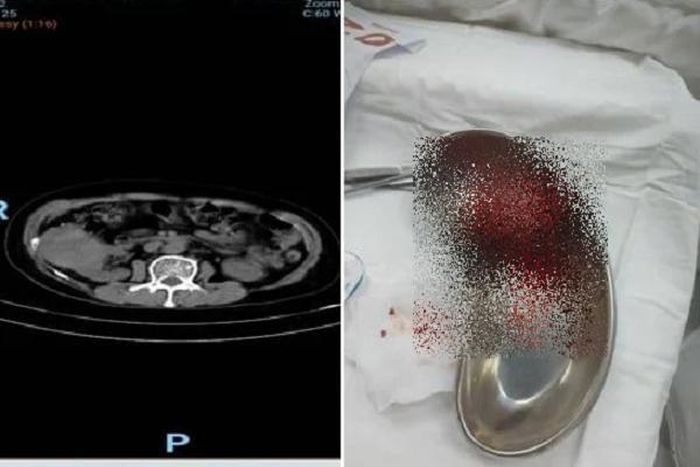

Kết quả chụp CT trước phẫu thuật (hình bên trái) và khối u thận sau khi lấy ra khỏi cơ thể bệnh nhân - Ảnh: BVCC

Các bác sĩ Bệnh viện Nhân dân 115 thực hiện siêu âm bụng thì phát hiện một khối u kích thước 75 x 60mm ở cực trên thận phải nữ bệnh nhân. Sau khi chụp CT có tiêm cản quang, khối u được chẩn đoán nghi ngờ là ung thư biểu mô tế bào thận (RCC) chưa có dấu hiệu xâm lấn ra ngoài thận trên hình ảnh học.

TS-BS Trương Hoàng Minh, Trưởng khoa Ngoại niệu - Ghép thận, Bệnh viện Nhân dân 115, cho biết ung thư biểu mô tế bào thận là loại ung thư thận phổ biến nhất, chiếm khoảng 90% các trường hợp ung thư thận ở người lớn. Bệnh thường gặp ở độ tuổi trung niên và người cao tuổi, với tỷ lệ nam giới mắc cao hơn nữ giới. Do RCC thường tiến triển âm thầm, nhiều bệnh nhân không có triệu chứng cho đến khi khối u lớn hoặc di căn, khiến việc chẩn đoán muộn và điều trị gặp nhiều khó khăn

“Rất may là bệnh nhân này bất ngờ được phát hiện kịp thời, các bác sĩ đã tiến hành can thiệp tắc mạch chọn lọc để giảm lượng máu nuôi khối u, sau đó thực hiện phẫu thuật nội soi cắt khối u bảo tồn phần nhu mô thận còn lại. Nhờ đó, bệnh nhân giữ được chức năng thận tối ưu và phục hồi nhanh chóng sau phẫu thuật”, bác sĩ Minh cho biết thêm.